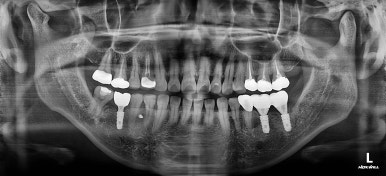

초진 시 X-ray 사진인데요.

이가 없는 뒤쪽 치아가 앞으로 쓰러져있고요. 맨 뒤에 사랑니까지 앞으로 쓰러져있네요.

이대로 임플란트도 못할 뿐더러 이대로 계속 지낸다면 쓰러진 치아에 계속 힘이 가해지니 치아 수명에 굉장히 안좋아요.

X-ray 사진으로 중간평가 해주고요.

적절한 자리가 마련되었다고 판단되면 임플란트 식립 가능성을 평가하게 됩니다.